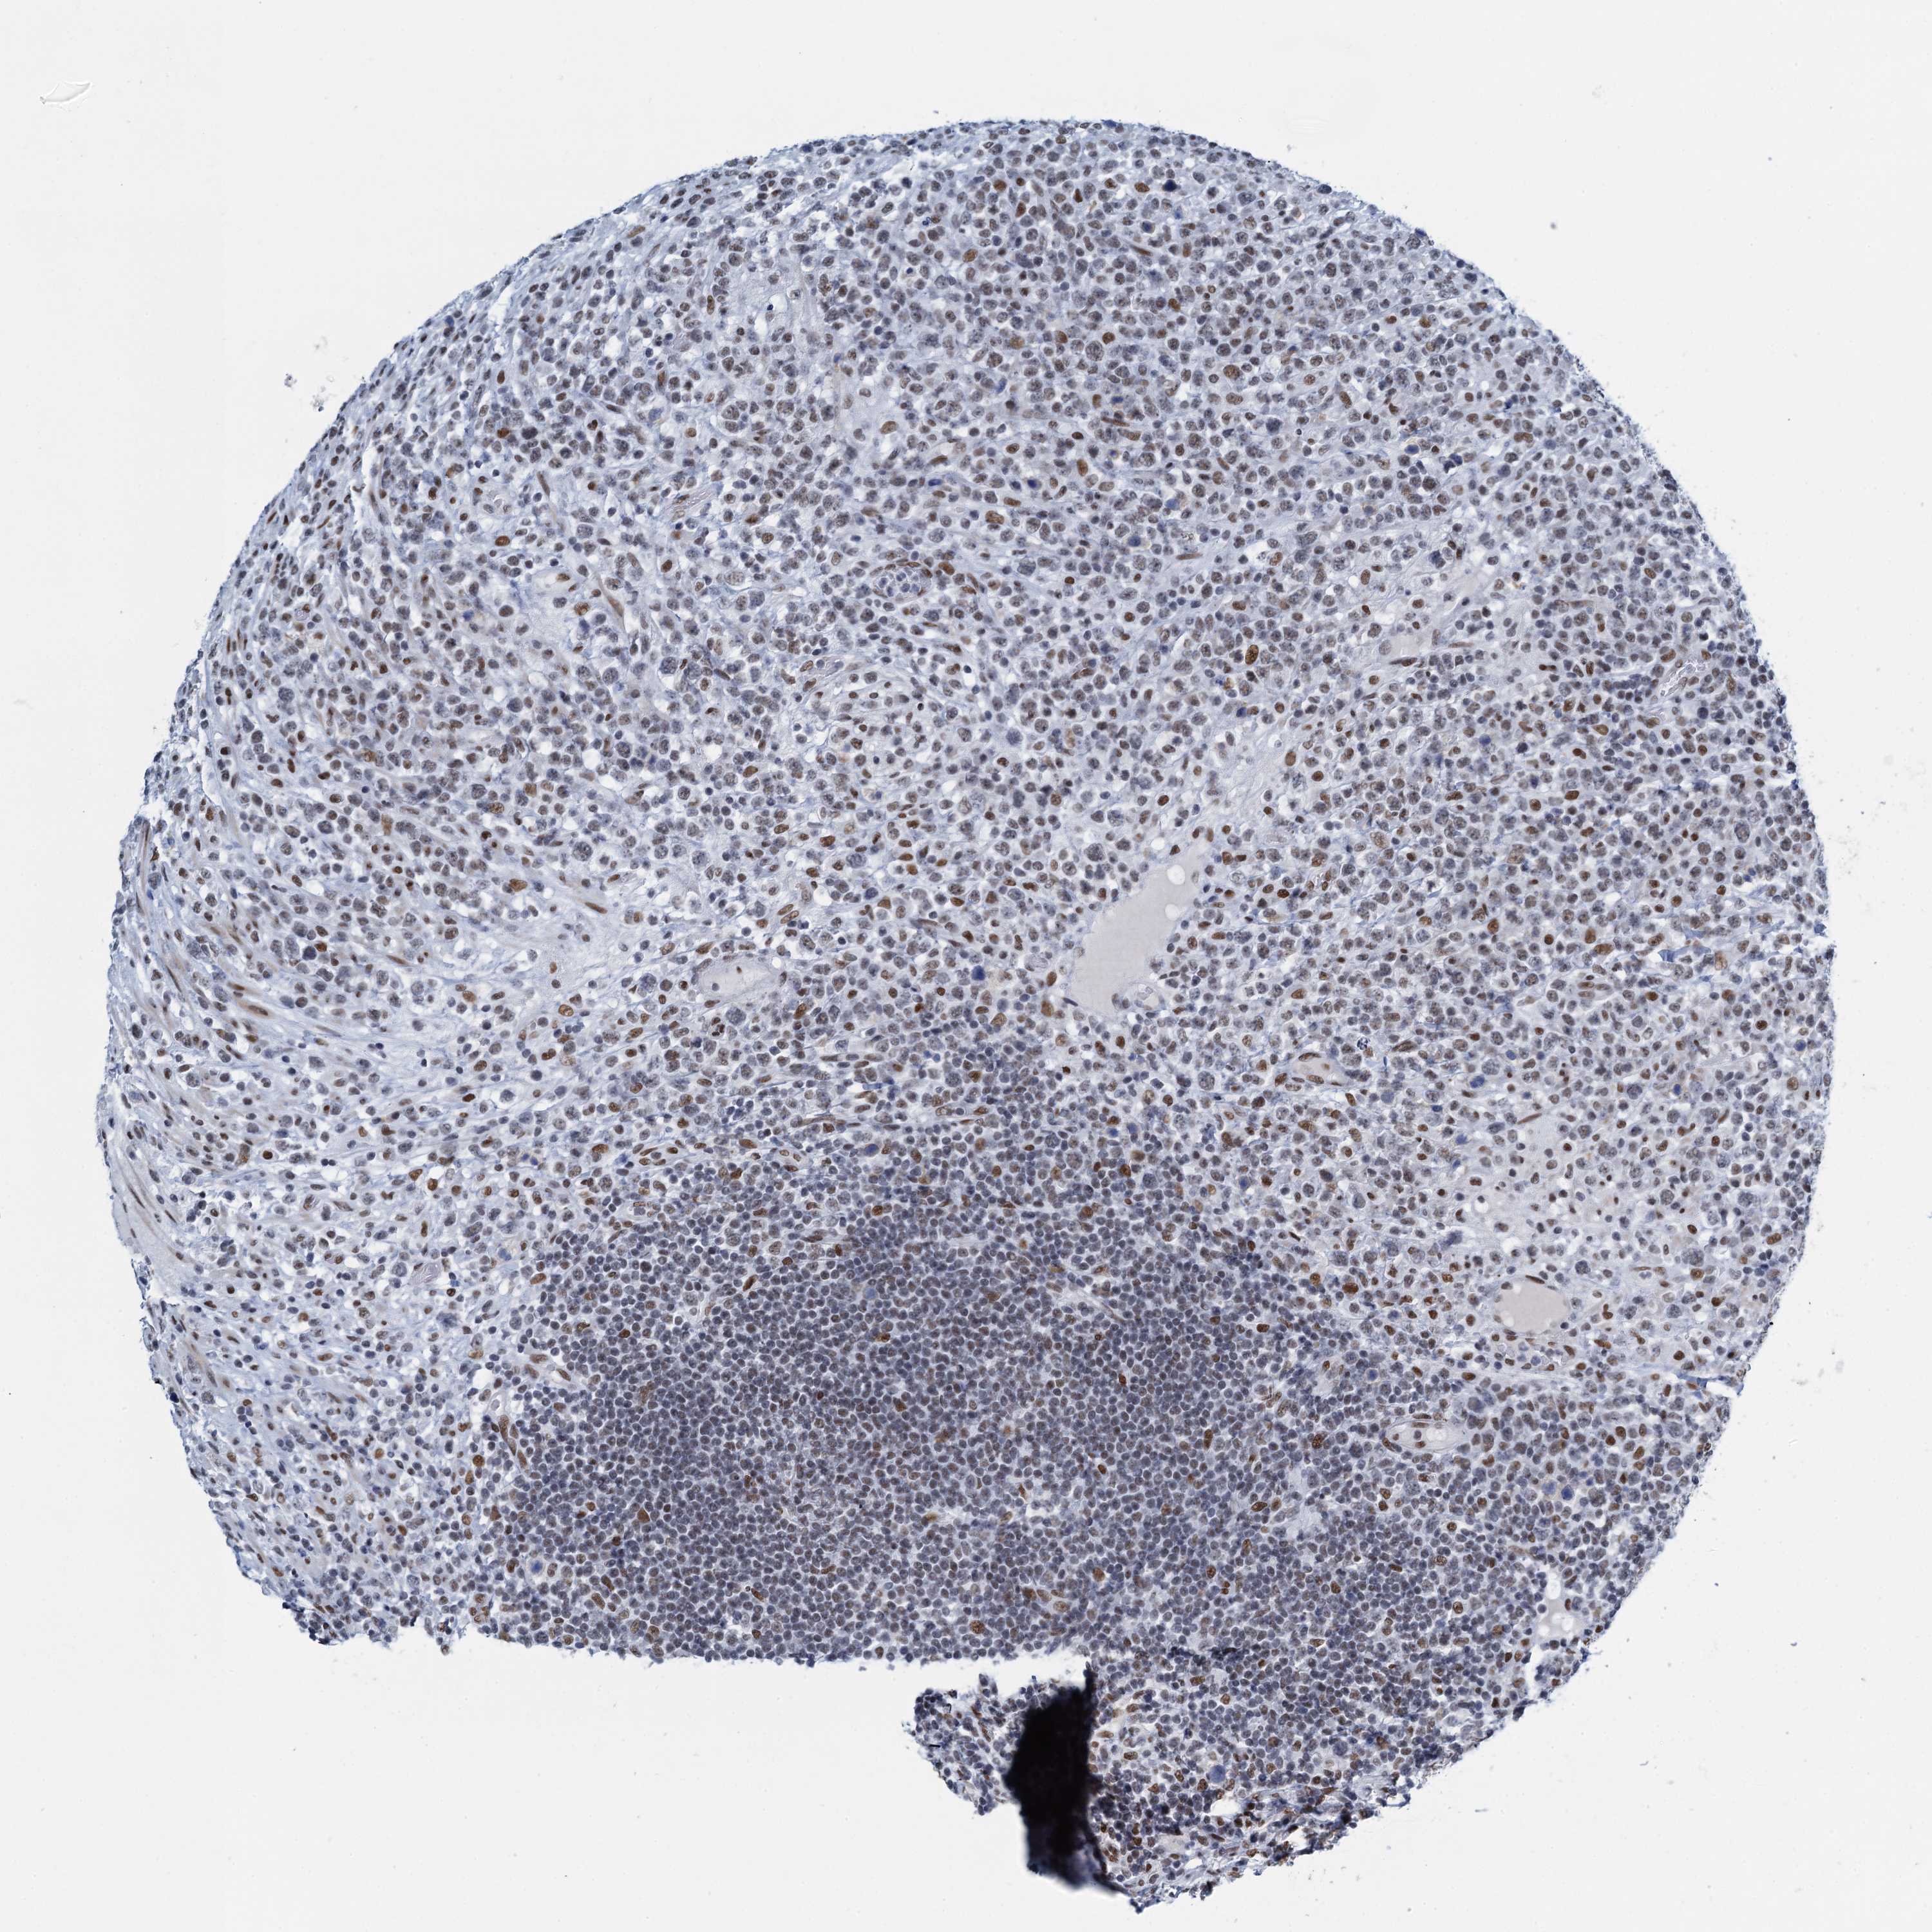

LYMPHOMA - Protein expressioni

A mouse-over function shows sample information and annotation data. Click on an image to view it in a full screen mode. Samples can be filtered based on level of antibody staining by selecting one or several of the following categories: high, medium, low and not detected. The assay and annotation is described here.

Antibody stainingi

Antibody staining in the annotated cell types in the current human tissue is reported as not detected, low, medium, or high, based on conventional immunohistochemistry profiling in selected tissues. This score is based on the combination of the staining intensity and fraction of stained cells.

Each image is clickable and will lead to virtual microscopy that enables deeper exploration of all samples and also displays staining intensity scores, fraction scores and subcellular localization as well as patient and tissue information for each sample.

Antibody HPA041632

Hodgkin's disease, NOS

Malignant lymphoma, non-Hodgkin's type, High grade

Malignant lymphoma, non-Hodgkin's type, Low grade